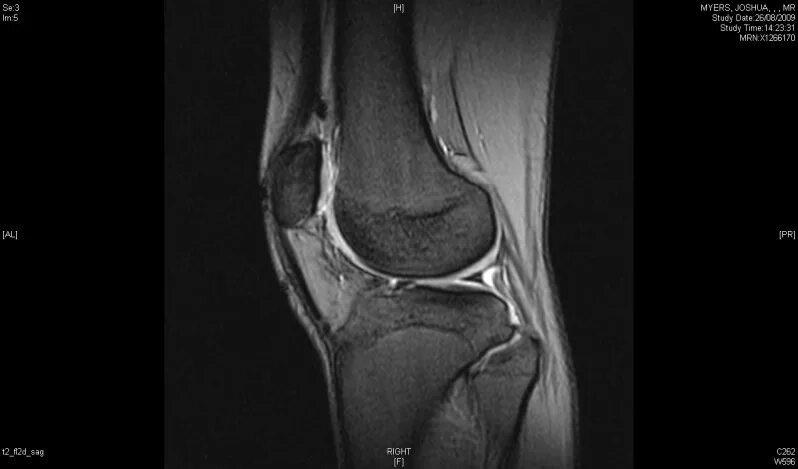

Мрт колена время